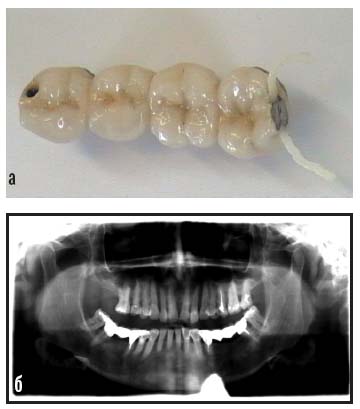

Со слов пациентки и по результатам внешнего осмотра выяснили: гигиенический уход за полостью рта осуществляется регулярно, зуб 24 удален по поводу осложненного кариеса около полугода назад, аллергоанамнез не отягощен, конфигурация лица не изменена, рот открывает свободно и в полном объеме, деформационных изменений зубных рядов нет; зубы 17, 16, 25, 27, 36, 45, 47 ранее лечены по поводу кариеса, 46 лечен по поводу осложненного кариеса и на панорамной рентгенограмме имеет эндодонтически обтурированные верхушки корневых каналов без периапикальных изменений, зубы 36 и 46 имеют разрушение окклюзионной поверхности – 70% (рис. 4).

Рис. 4. Клиническая картина до протезирования – а, б

По данным ортопантомограммы: генерализованная деструкция альвеолярной кости с резорбцией в области жевательных зубов до 1/2 длины корня (рис. 5). Патологическая подвижность зубов по Энтину I, II степени.

Рис. 5. Ортопантомограмма зубочелюстной системы до протезирования